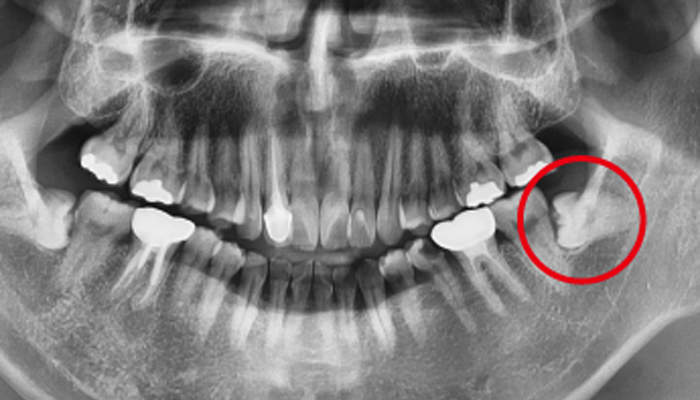

사랑니 발치 전후 사례

• 치료 전

치료 후